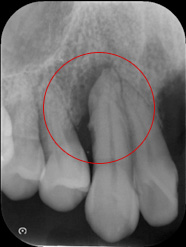

赤丸の部位は根元まで骨がありませんが、隣の歯に骨があるのでエムドゲインによる再生療法の適応症です。